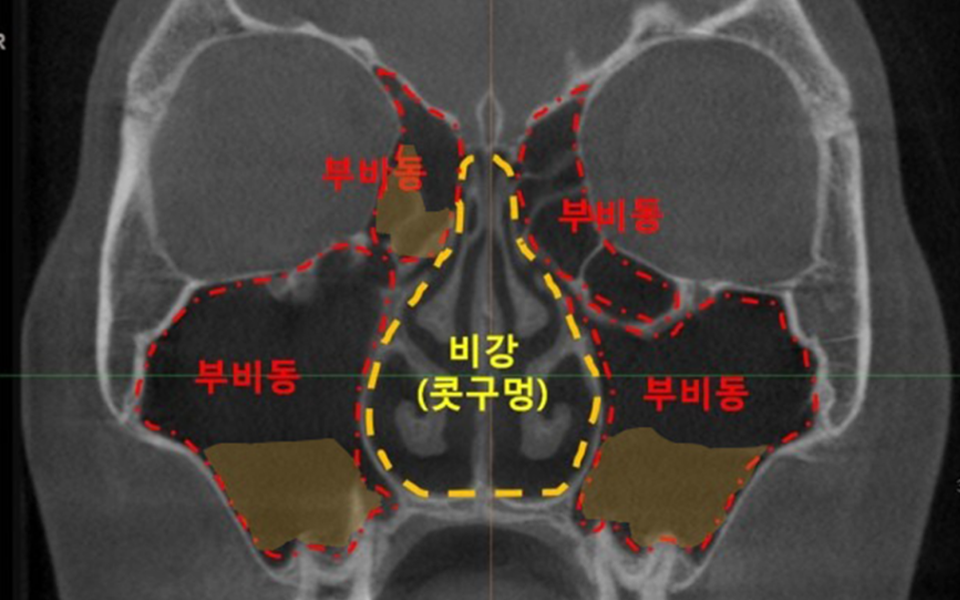

축농증 때문에 지긋지긋하고 고생하고 계시다면 우선 부비동의 구조부터 파악해서현재의 내가 어떤 상태인지 명확히 아는...

축농증이란?축농증은 의학적으로 부비동염이라고 하며, 코 주변에 위치한 부비동이라는 공간에 염증이 생기는 질환입니다...